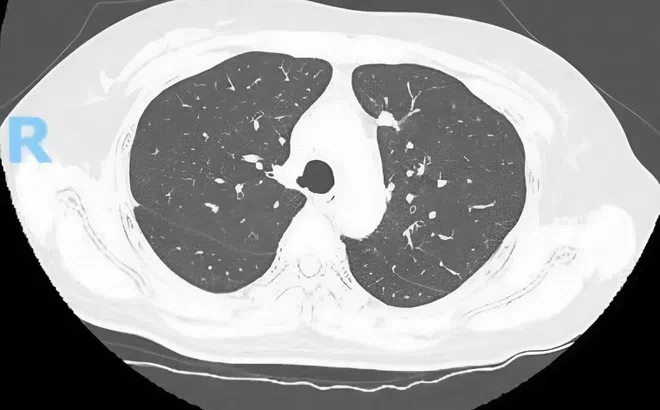

Bất ngờ phát hiện mắc ung thư từ nốt mờ nhỏ ở phổi

Chỉ từ những nốt mờ nhỏ tình cờ phát hiện khi tầm soát sức khỏe, hai bệnh nhân ở TP.HCM được chẩn đoán ung thư phổi giai đoạn sớm và kịp thời điều trị triệt để.